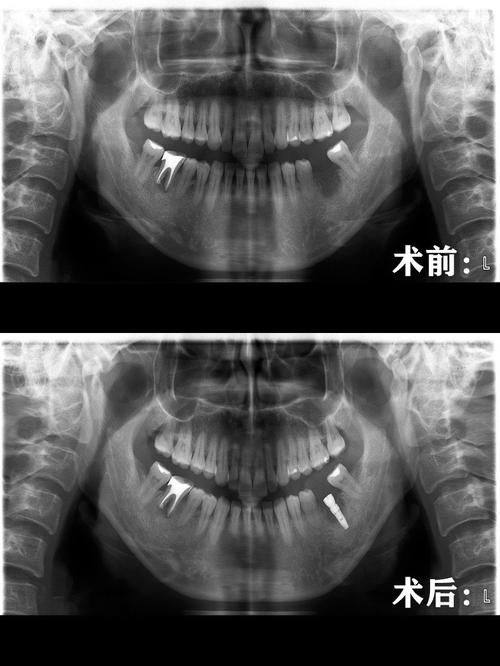

"之前缺了一颗牙,吃饭特别不方便,在雅芝口腔做了种植牙。术前医生用全景片设备做了详细检查,制定了个性化方案,手术过程特别顺利,修复得也特别快。现在种植牙用着和真牙差不多,吃饭完全不受影响,医生还定期回访我的修复情况,真的特别贴心,给诊所的技术和服务点个赞。"